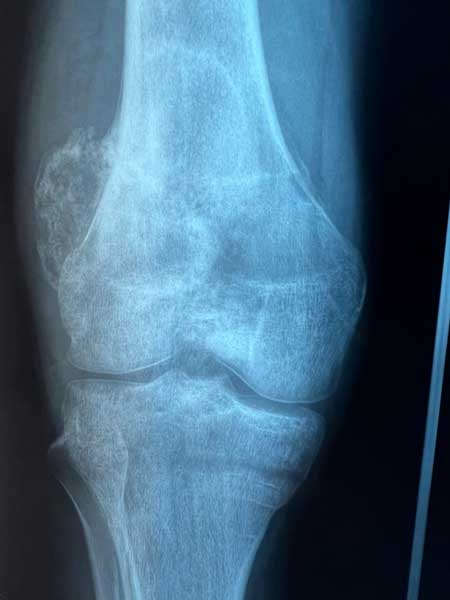

Dès 2006, il a démontré la possibilité de réaliser simultanément deux prothèses de hanche sur le même patient (références 23 à 28), stratégie qui est désormais utilisée par le Docteur Jean-Luc Raynier, et il a mis en évidence les limites des cupules de resurfaçage de hanche (référence 29). Il est également spécialiste de la reconstruction osseuse par Ingénierie tissulaire, sujet de sa thèse de science, objet de nombreuses publications internationales depuis 2005 (références 30 à 36). Enfin, le Professeur Trojani est spécialisé dans les interventions exceptionnelles en chirurgie tumorale, au niveau du genou et du bassin (Figures 3 à 5).

Figure 3 : chirurgie de résection complète du fémur avec mise en place d’une prothèse de fémur total, c’est-à-dire simultanément d’une prothèse de hanche et d’une prothèse de genou, du fait d’une tumeur osseuse atteignant tout le fémur (Sarcome d’Ewing).